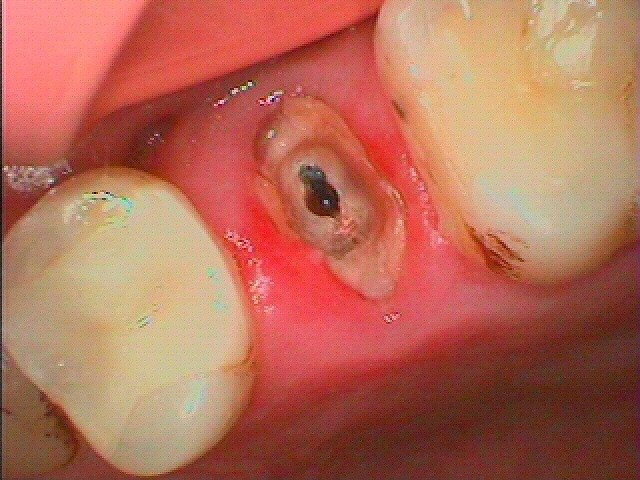

ソウハして埋めただけのインプラント埋入になります。| |広島市安佐南区の歯科医院 ソウハして埋めただけのインプラント埋入になります。 トップ お知らせ・ブログ ソウハして埋めただけのインプラント埋入になります。 ソウハして埋めただけのインプラント埋入になります。 Web診療予約 初めての方へ 選ばれ続ける理由 院内設備について 歯が痛いしみる一般歯科 歯がぐらぐらする歯周病 健康な歯を保ちたい予防歯科 子供の虫歯予防をしたい小児歯科 銀歯をセラミックに審美歯科 白い歯を目指しませんか?ホワイトニング 矯正専門医がいるので安心矯正歯科 抜けた歯を補いたいインプラント・入れ歯 医院案内 スタッフ紹介 メリィハウス歯科クリニックオフィシャルホームページ ラベンダー歯科クリニックオフィシャルホームページ お知らせ・ブログ ホーム 診療科目 一般歯科 歯周病治療 予防治療 小児歯科 審美治療 ホワイトニング 矯正歯科 入れ歯・インプラント マウスピース矯正 初めての方へ 院長・スタッフ 設備紹介 医院案内・アクセス メニューを閉じる